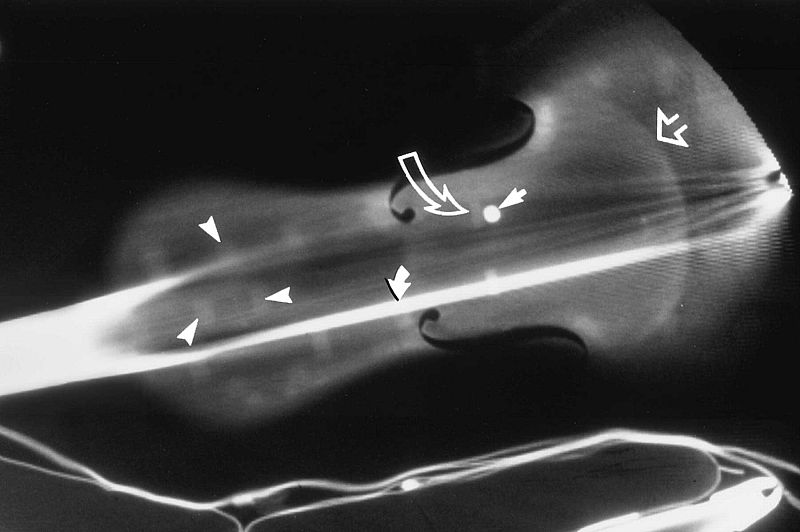

El equipo de investigadores estadounidenses usaron la tomografía computerizada (TC) en este instrumento de más de 300 años para revelar sus secretos. "La TC ofrece un método único, no invasivo, de la imagen de un objeto histórico", afirma Steven Sirr, radiólogo en FirstLight Medical Systems en Minnesota (Estados Unidos), "combinada con maquinaria asistida por ordenador, también ofrece la oportunidad de crear una reproducción con un alto grado de precisión".

El violín original, perteneciente a la Biblioteca del Congreso de EE.UU., fue escaneado y se tomaron más de 1.000 imágenes bajo los rayos X. Después se convirtieron en un formato de archivo para ser leidos por un ordenador en tres dimensiones. Los datos extraídos sirvieron para tallar las piezas de madera cuidadosamente escogidas que fueron luego ensambladas por los dos artesanos expertos en violines y barnizadas a mano.

El responsable de la investigación, violinista aficionado, escaneó por primera vez un violín mediante TC por curiosidad. "Creía que el instrumento no era más que una cáscara de madera que rodea el aire", dijo. "Estaba totalmente equivocado. Había un montón de anatomía interior en el violín".

Después de haber compartido esas primeras imágenes de la TC con Waddle en 1989, los dos pasaron años de exploración de más de 100 violines, entre ellos 29 valiosos instrumentos anteriores a 1827 y otros instrumentos de cuerda para entender mejor su composición.

Para los propietarios de los violines Stradivarius y otros preciados instrumentos, la TC no sólo proporciona una forma definitiva de identificación, también ayuda a establecer un árbol genealógico que pueden aumentar el valor de su inversión. "La TC es útil para medir la densidad de la madera, el tamaño y forma, grosor y graduación de las medidas de volumen," dijo Sirr. "También proporciona un análisis detallado de los daños y la reparación".